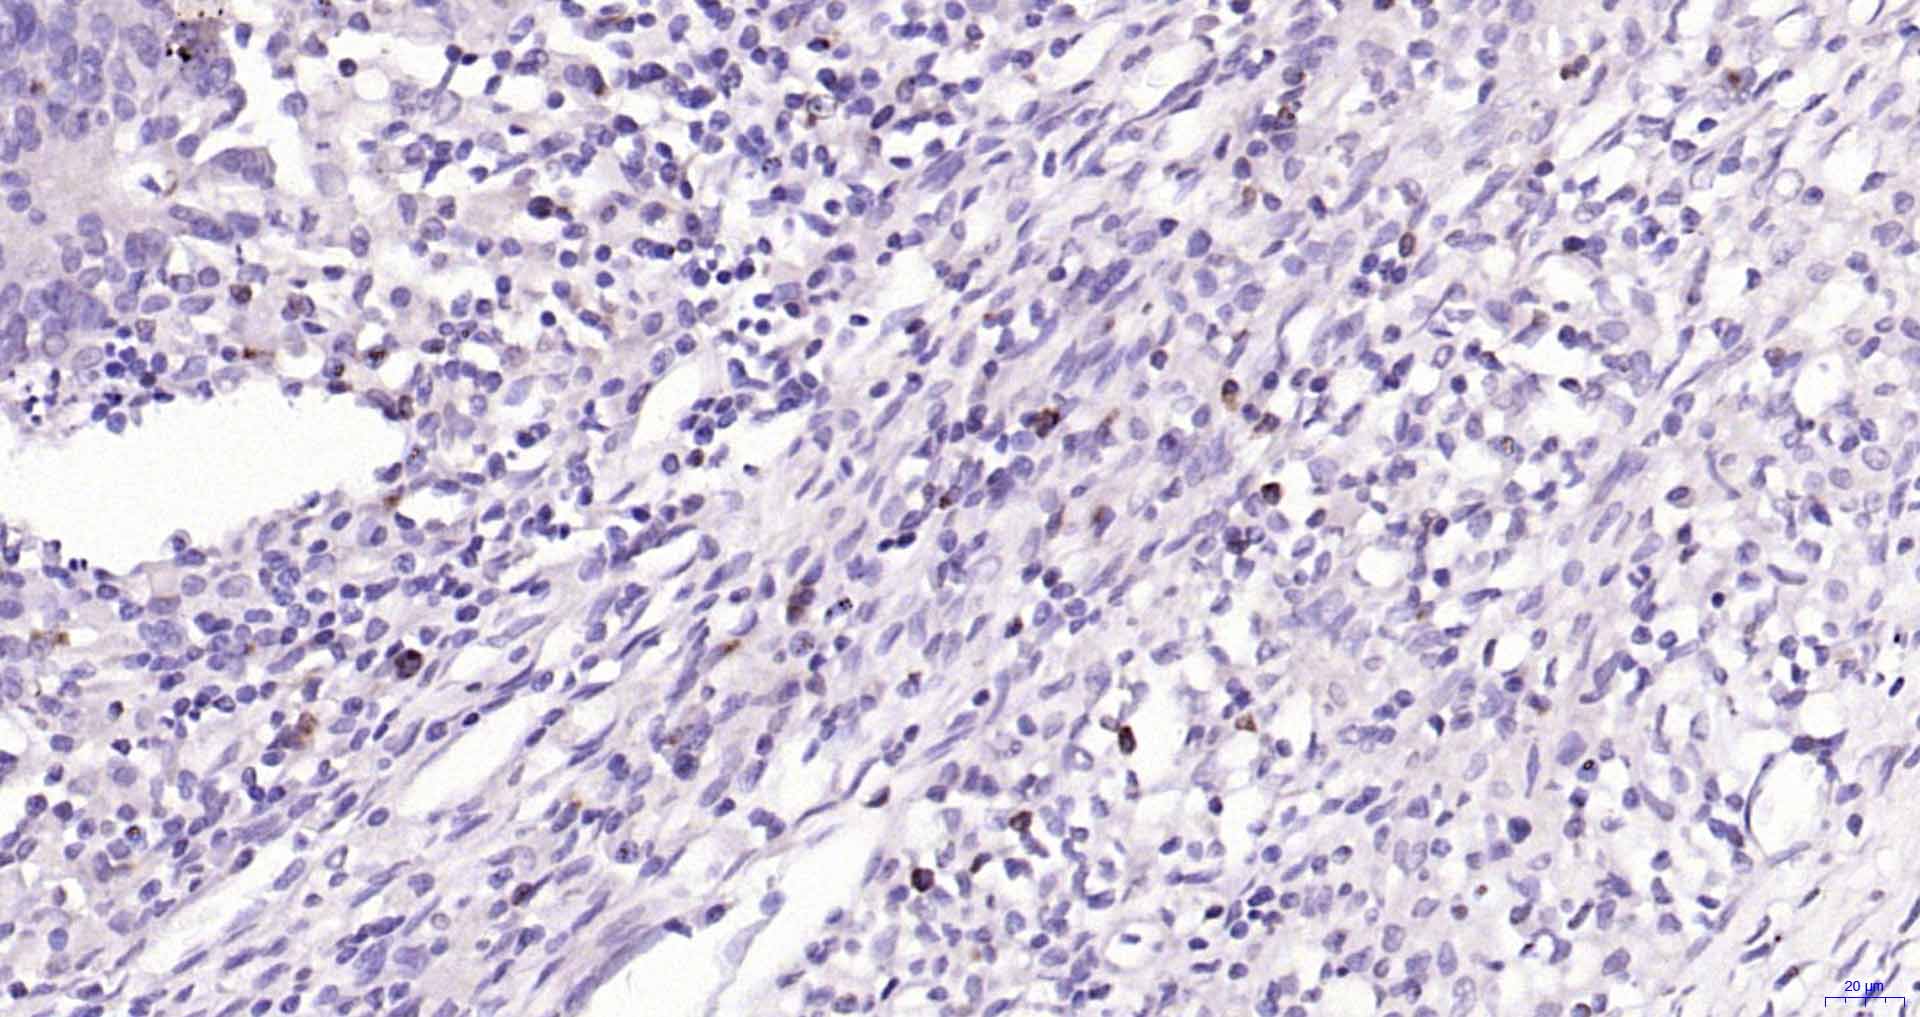

Paraformaldehyde-fixed, paraffin embedded Human Colon Cancer; Antigen retrieval by boiling in sodium citrate buffer (pH6.0) for 15 min; Antibody incubation with Granzyme B Monoclonal Antibody, Unconjugated(bsm-60779R) at 1:300 overnight at 4°C, followed by conjugation to the SP Kit (Rabbit, SP-0023) and DAB (C-0010) staining.